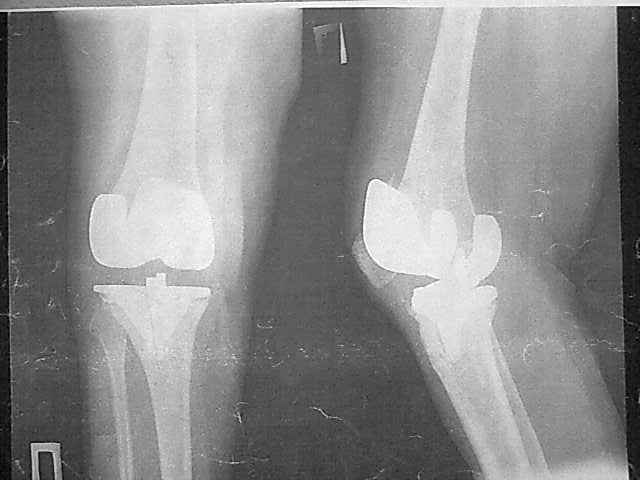

Уважаемые коллеги, прошу Вашего совета по тактике лечения. Женщина 1952 г.р., оперирована в 2006, в одной клинике установлен эндопротез правого коленного сустава, через год нестабильность обоих компонентов, доктор выполняет ревизию обычным протезом с задним стабилизатором. В октябре 2008 - нестабильность, свищ. В другом стационаре все удалено, спейсер с гентамицином, длинный курс антибиотиков. Коллатеральных связок нет. Собственная связка надколенника цела. До удаления протеза - выраженная смешанная контрактура. Сейчас свищей нет, анализы в порядке.

Планы: Стоит выбор 1) Обычный hinge с цементными ножками, вставками под тибиальным и бедренным компонентами с импакционной костной пластикой аллокостью с применением сеток для удержания трансплантата на tibia; 2) Онкологический hinge - с замещением проксимальной голени и сохранением бедра; 3 - артродез.

Мне очень хотелось узнать мнение коллег на предмет - если ставить простой hinge с костной пластикой - стоит ли использовать только костную крошку или необходим структурный костный аллотрансплантат? Есть ли у кого-то положительный опыт таких операций? Душа у меня не лежит использовать онкологическим протез для голени, т.к. пациентка слишком молода и сохранена собственная связка надколенника.